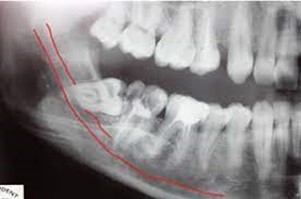

what can mandibular third molars be impacted against

A

adjacent tooth

alveolar bone

surrounding mucosal soft tissue

or combination of these factors

incidence of impacted lower third molars